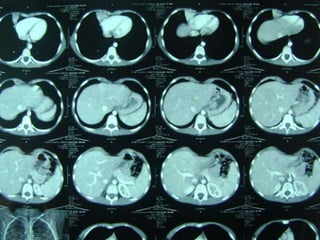

 LA TAC puede lograr

sospecha

 La Angio-TAC pulmonar

confirma al diagnóstico.

 Angiografía y el

Ecodoppler color, que

pueden mostrar la

irrigación sistémica del

secuestro.

OTRAS IMÁGENES  LATAC puede lograr sospecha  La Angio-TAC pulmonar confirma al diagnóstico.  Angiografía y el Ecodoppler color, que pueden mostrar la irrigación sistémica del secuestro.